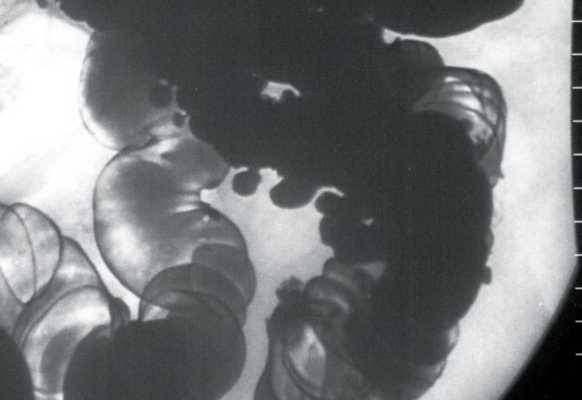

При ирригоскопии, проведенной через 4 нед после выписки пациентки из стационара (рис. 5), толстая кишка исследована в условиях двойного контрастирования. Бариевой взвесью и воздухом заполнились все отделы и обычно расположенный червеобразный отросток. В тонкую кишку бариевая взвесь не проникла. Сигмовидная кишка была удлинена. Расположение петель обычное, контуры ровные, четкие, стенки эластичные. Гаустрация хорошо выражена, в левой половине неравномерная. В левой половине, преимущественно в сигмовидной кишке, выявлены множественные разнокалиберные дивертикулы, в области печеночного изгиба - одиночные мелкие дивертикулы. Деформаций кишки, сужения просвета, внутрипросветных образований не обнаружено. Опорожнение кишки неполное, неравномерное. Заключение: дивертикулез толстой кишки с преимущественным поражением левых отделов.

Рис. 5. Рентгенологическая картина дивертикулеза толстой кишки. Ирригоскопия в условиях двойного контрастирования.